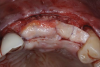

This approach was effective in increasing the horizontal and vertical soft-tissue thickness around the three implants. Nevertheless, a distortion of the MGJ was still present (Figure 13). Therefore, 3 months after the iCTG augmentation, it was decided to perform a second soft-tissue augmentation procedure with the goal of repositioning the MGJ in an adequate level on the buccal aspect, increasing the width of the keratinized mucosa at the implant sites. A modified apically positioned flap was performed (Figure 14). Two labial strip gingival grafts were harvested from the anterior mandible and maxilla and sutured onto the recipient bed with a 7-0 polyglycolic acid resorbable suture.5,17,18 The residual periostium was covered with a non-crosslinked xenogeneic collagen matrix (Figure 15).

Fig 13. Distortion of the mucogingival junction.

Figure 13

Fig 14. Modified apically positioned flap.

Figure 14